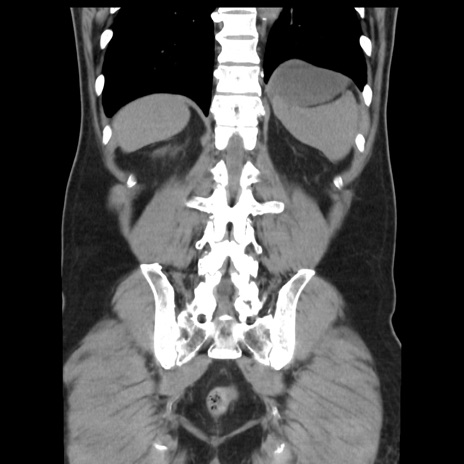

症例16(冠状断像)

【症例】 70歳代男性

【主訴】 腹痛、嘔吐

【現病歴】 約1ヶ月前より間欠的に腹痛と嘔吐あり、当院消化器内科を受診したところCTで多発する肝臓のLDAを指摘され、精査中であった。以降は消化器症状は安定していたが、2日前より嘔気と腹痛があり、同日より排便・排ガスが消失した。改善認めず、 本日、救急外来を受診した。

【既往歴】 大腸ポリープ切除後。

【身体所見】意識清明・会話良好、BT 36.3℃、BP 127/80mmHg、 P 80bpm、腹部:膨満あり、平坦・軟、上腹部正中および下腹部正中に圧痛あり、反跳痛なし、筋性防御なし。

【データ】WBC 7200、CRP 0.77